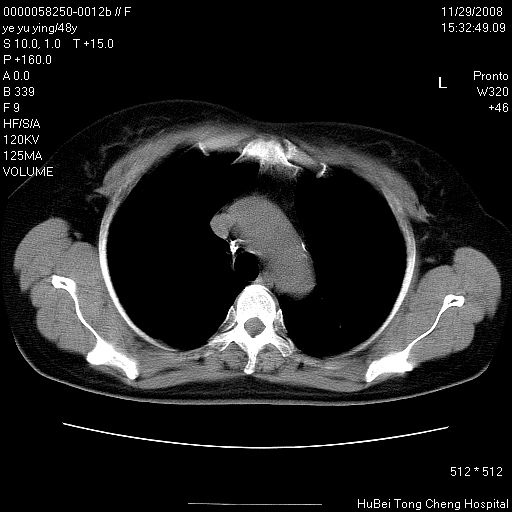

以下是引用zsl6918在2008-11-29 21:47:00的发言:[br]恶性肿瘤病史,转移瘤首先考虑。脂肪肝,胆囊结石。

以下是引用huenhao在2008-11-29 22:11:00的发言:[br]脂肪肝,胆囊结石。左肺病灶建议定期复查。

以下是引用liuyue在2008-11-30 5:44:00的发言:[br]1.左肺病变,首先考虑感染性病变,转移待排;建议治疗后复查。[br]2.肝脏密度普遍减低,考虑与化疗有关。[br]3.胆囊结石.